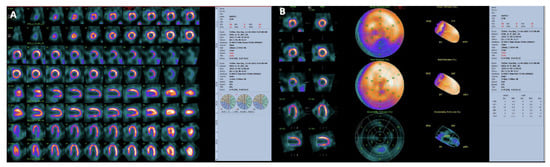

Several perfusion and nonperfusion markers have been proposed to improve detection of left main or three-vessel coronary disease [84,93]. Risk assessment with SPECT MPI is improved if functional assessments from ECG-gated SPECT measurements of ejection fraction and end systolic volume are considered. Additionally, transient ischemic dilation of the left ventricle can be evaluated. [94] Each of these measurements are important nonperfusion predictors of severe CAD [95,96]. The demonstration by SPECT imaging of significant, inducible myocardial ischemia to indicate viability, not only defines a high cardiovascular risk for a specific patient, but can also guide treatment to improve outcome. Observational studies with long-term follow-up suggested that ischemia on SPECT-MPI could identify high-risk patients who might have reduced mortality with early revascularization compared to medical therapy [97,98,99]. Recently, there is a trend toward shorter acquisition times and reduced radiation exposure for SPECT MPI [100]. Alternative imaging modalities and improved reconstruction algorithms have emerged for this purpose and a new solid-state detector technology [101], such as cadmium-zinc-telluride detectors, has been introduced for dedicated cardiac SPECT systems (CZT SPECT) [102]. Moreover, CZT SPECT through fast dynamic tomography provides some new parameters for quantitative analysis of absolute myocardial blood flow (MBF) and myocardial flow reserve (MFR), which may improve the detective sensitivity and avoids missed diagnosis or underestimation [103,104]. A representative case has shown in Figure 7.

Figure 7.

Myocardial perfusion SPECT with Tc-99m-Tetrofosmin in a patient with CAD performed at stress (maximal cycloergometer exercise) and at rest. Stress and rest slices in three axes are shown in (Panel (A)). Polar maps under stress and at rest are shown in (Panel (B)). Slices and polar maps show a stress perfusion defect in the inferior wall which significantly improves (reverses) in the rest study. The pattern is typical of stress-induced myocardial ischemia.